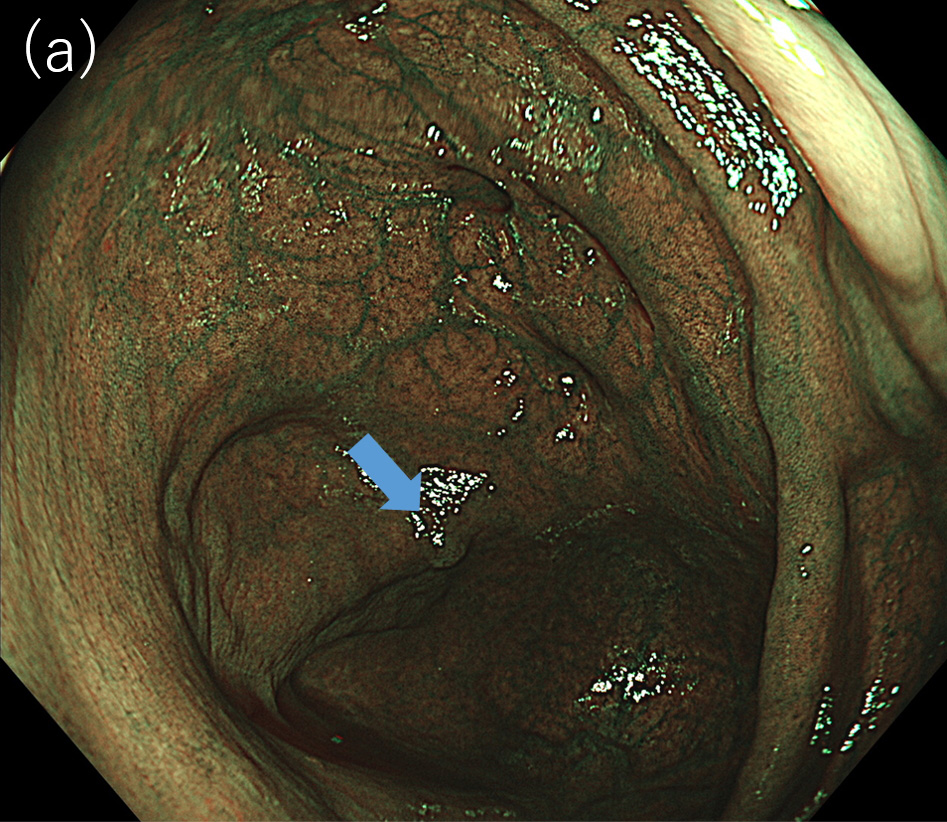

〈図2〉 XZ1200による同一病変に対するNBI中遠景観察像(a)BAI-MAC OFF; (b)BAI-MAC ON